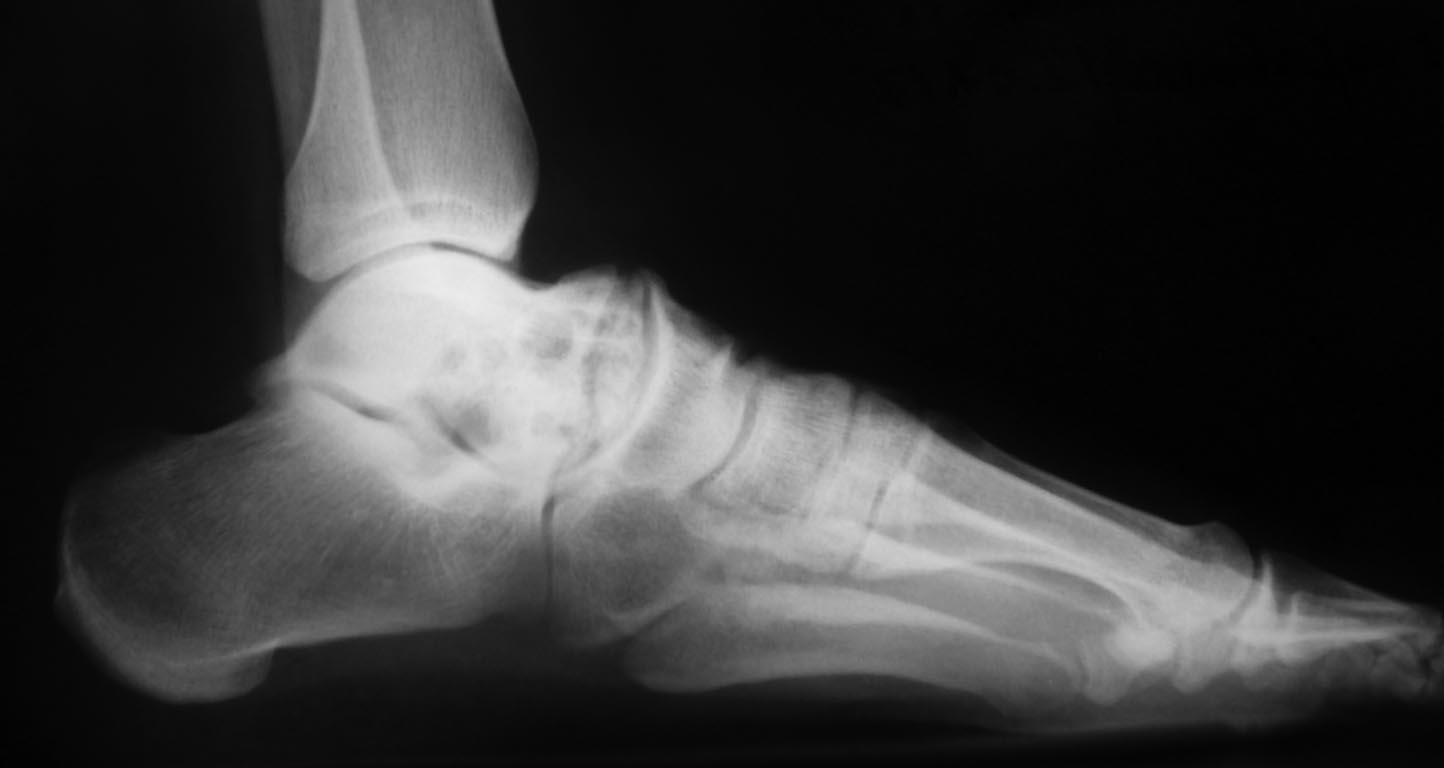

Здравствуйте, глубокоуважаемые участники форума. Прошу Вас о помощи в , на наш взгляд, не простом случае заболевания среднего отдела стопы у ребёнка 16 лет. Девушка имеет солитарную кисту головки и шейки таранной кости стопы. Обратилась и госпитализирована с болями в среднем отделе стопы. Ребёнок 16 лет. Направляющий диагноз: "Солитарная киста головки и шейки таранной кости стопы".Гистологический диагноз выставлен на основании пункционной биопсии в одной из авторитетнейших онкологических клиник Москвы. Выполненное лечение - инъекция Коллатампа - апрель 2017г. .

Ходит без ортеза. Жалуется на боли в области Шопарова сустава. Свод стопы сохранён. Тест "на носочках"-выполняет 15-20 секунд, жалуясь на возрастающие боли. Походка не нарушена. Может пройти 1 км пешком. Девушка крупного телосложения. Атрофии мышц голени нет. Пальпаторно - болезненность в области тыльной поверхности стопы в таранно-ладьевидного сустава. Движения в голеностопном суставе - в полном объёме. Результаты исследований будут в приложениях.

Кисту не стоит побеждать. Боимся, конечно, патперелома. И и она там не нужна совсем. Но дело не в этом. Идёт пластическая деформация по линии таран-ладья и там же болит. И там же перестройка кости, которая закончится с непредсказуемым результатом. Боимся потери свода , усиления болей , хромоты , которая может прогрессировать годами,

Максим, спасибо за совет. Но это просто про кисту. Конечно, мы её вылечим стероидами. Но, пока это случится, шейка тарана окончательно раствориться и сплющенная головка установится ещё выше ладьевидной коси и блока тарана. У девочки, подчеркну, и так уже болит при стоянии и ходьбе.Есть артроз смежных суставов. Проблема не в способе лечения кисты, а в способе стабилизации стопы и оптимальной стратегии на ближайшие 5 лет. Наша задача - стабилизировать свод и опорную функцию стопы. Дать возможность ходить человеку с более ранней нагрузкой и использовать стопу как стопу. На наш взгляд, артродезы, аутопластика и стабильный остеосинтез неизбежны.